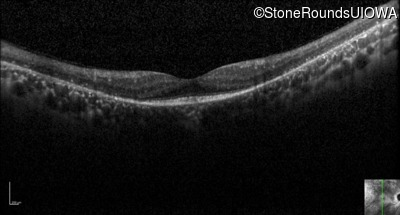

Optical Coherence Tomography - Right - 20/25

Exemplar / OCT Stack